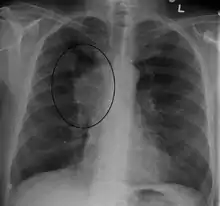

Diagnosis

The main techniques of diagnosing SVCS are with chest X-rays (CXR), CT scans, transbronchial needle aspiration at bronchoscopy and mediastinoscopy.[5] CXRs often provide the ability to show mediastinal widening and may show the presenting primary cause of SVCS.[5] However, 16% of people with SVC syndrome have a normal chest X-ray. CT scans should be contrast enhanced and be taken on the neck, chest, lower abdomen, and pelvis.[5] They may also show the underlying cause and the extent to which the disease has progressed.[5]